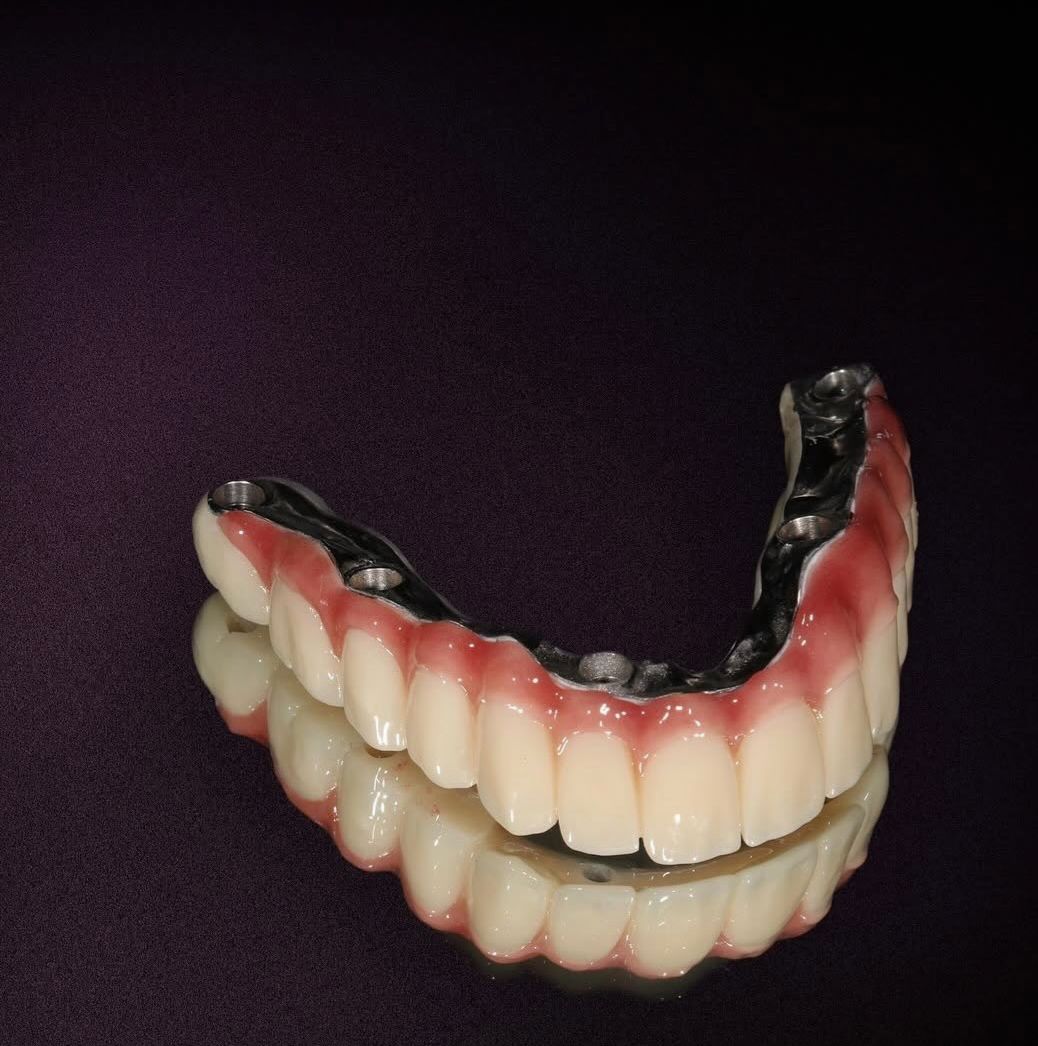

İmplant tedavisi

İmplant Tedavisi ile Kalıcı ve Güvenli Çözüm

İmplant tedavisi, eksik dişlerin yerine çene kemiğine yerleştirilen titanyum vidalar sayesinde doğal diş fonksiyonunu yeniden kazandıran modern ve kalıcı bir yöntemdir. Kemikle biyolojik uyum sağlayan implantlar, üzerine yerleştirilen protezlerle birlikte hem estetik hem de fonksiyonel açıdan güçlü bir sonuç sunar.

Eksik dişler zamanla kemik kaybına ve çevre dişlerde bozulmaya neden olabilir. İmplant tedavisi, kemik yapısını destekleyerek bu sürecin önüne geçmeye yardımcı olur. Sağlam bir temel, sağlıklı ve özgüvenli bir gülüş demektir.